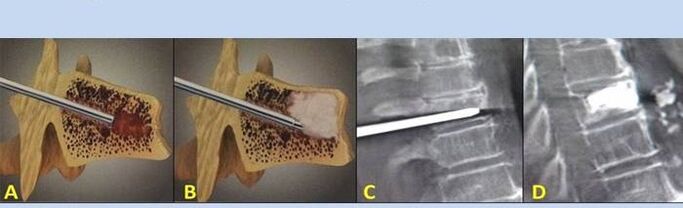

- Nucleoplastie – verwijdering van de kern van de tussenwervelschijf. De operatie verlicht de druk op de zenuwuiteinden.

- Punctie vertebroplastie – methode om de wervels te stabiliseren. Tijdens de procedure vult de arts de holtes van de wervelkolom met botcement.